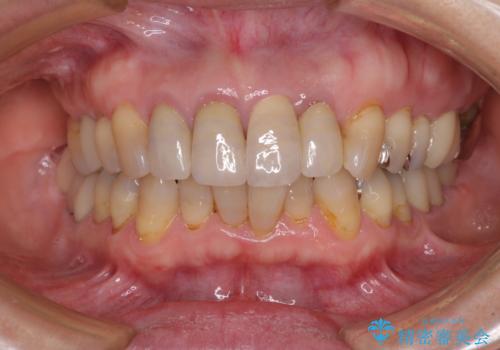

3. 折れてしまった前歯 インプラントによる補綴治療の治療後